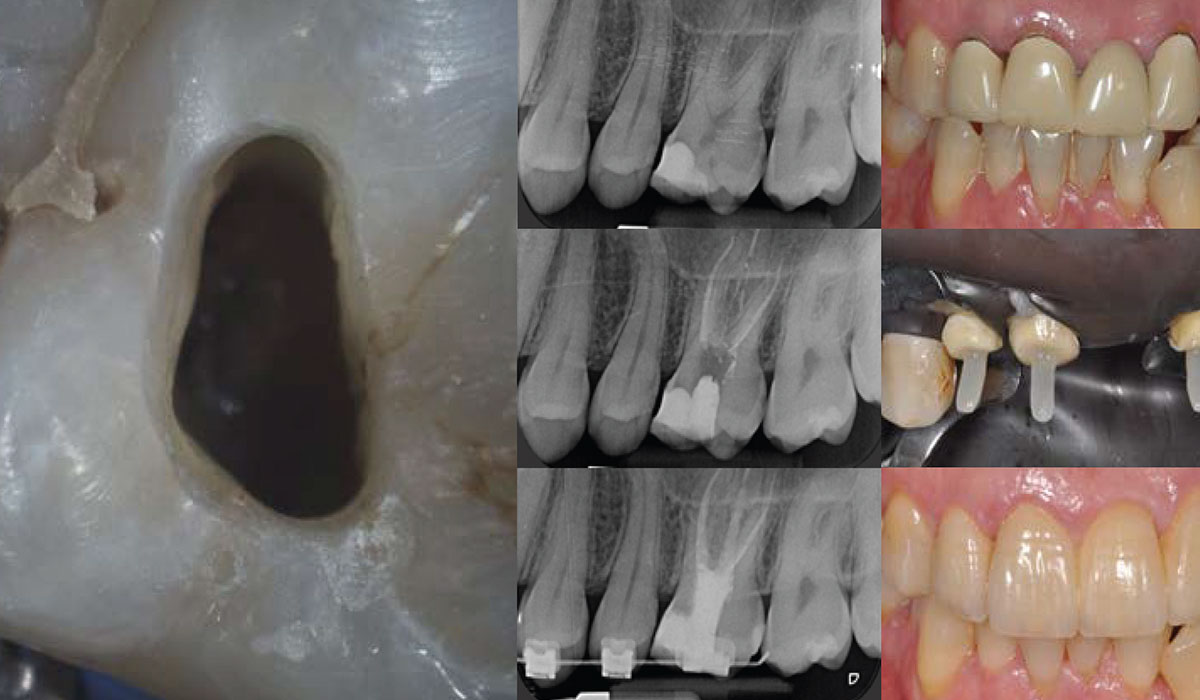

1° giorno - ARGOMENTI ENDO

• Diagnosi in Endodonzia.

• L’importanza dell’utilizzo del Microscopio e sistemi ingrandenti.

• L’importanza della ricostruzione pre-endodontica e il trattamento del deep cervical margin.

• Cavità d’accesso: quali strumenti.

• Sondaggio del canale radicolare.

• Come utilizzare in modo corretto i rilevatori d’apice e i nuovi motori endodontici.

• Preflaring manuale e meccanico.

• Sagomatura del canale radicolare con strumenti rotanti e reciprocanti.

• La rifinitura apicale.

• Gestione di anatomie complesse, confluenze, canali a C e accessori.

2° giorno - ARGOMENTI ENDO

• Detersione: i principi base per una corretta disinfezione dei canali radicolari.

• Il miglioramento dei protocolli di debridement e disinfezione del canale radicolare.

• I Ritrattamenti:

– I fattori prognostici in Endodonzia.

– Il disassemblaggio coronale.

– La ricerca e il trattamento dei canali non trattati.

– La rimozione dei materiali da otturazione ed il superamento dei gradini.

– Tecniche a caldo e bioceramici a freddo.

3° giorno - RESTAURI POST-ENDO - PARTE PRATICA

• Cause di frattura del dente trattato endodonticamente.

• Criteri di scelta per il dente trattato endodonticamente.

• Valutazione della restaurabilità degli elementi.

• Criteri di scelta per l’utilizzo dei perni in fibra nelle ricostruzioni del dente trattato endodonticamente.

• Lo sbiancamento del dente devitale.

• La ricostruzione diretta del dente trattato endodonticamente nei settori posteriori.

• La ricostruzione diretta del dente trattato endodonticamente nei settori anteriori.

• Le differenti opzioni terapeutiche:

– Restauri adesivi estetici (diretti e indiretti).

– Restauri protesici